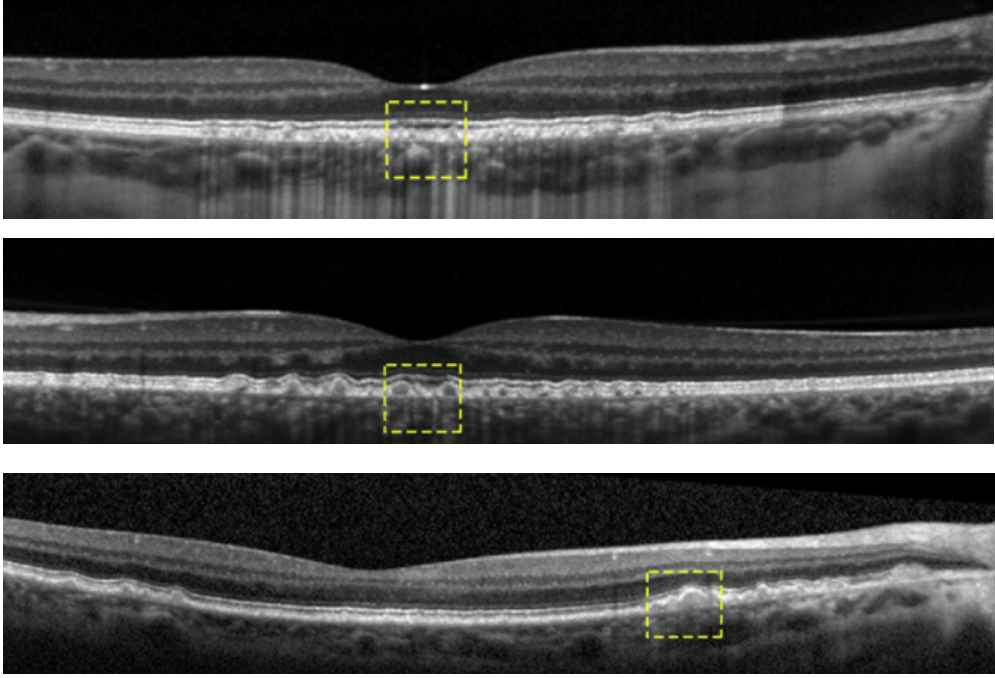

糖尿病患者眼底发现“星空样”玻璃疣

一名57岁的女性糖尿病患者,糖尿病病史12年,既往无眼科疾病。患者因近期双眼逐渐视物不清伴右眼视物变形5年(曾被患者忽视)到眼科就诊。眼科检查显示:右眼最佳矫正视力0.2,左眼0.4。双眼眼前节检查未见异常。眼底检查可见双眼黄斑至周边区域散在均匀的黄色小型玻璃疣,并伴有中心凹反光消失(图1)。

图1. 眼底照片显示双眼多处对称分布的玻璃疣,中心凹反光消失。